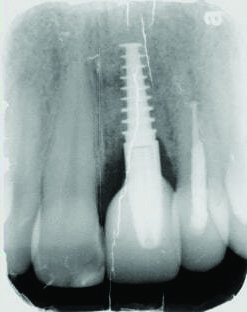

Fig 15 and Fig 16. Case 2: Clinical view (Fig 15) and radiograph (Fig 16) at 12-month follow-up confirming resolution of the peri-implant defect.

Figure 15

Fig 16. Case 2: Clinical view (Fig 15) and radiograph (Fig 16) at 12-month follow-up confirming resolution of the peri-implant defect.

Figure 16

The 12-month and 7-year follow-ups for case 2 showed similar improvements with normal soft-tissue healing and bone fill and normal pocket depths at 12 months (Figure 15 and Figure 16) and 7 years post-treatment (Figure 17 and Figure 18) (Table 1).